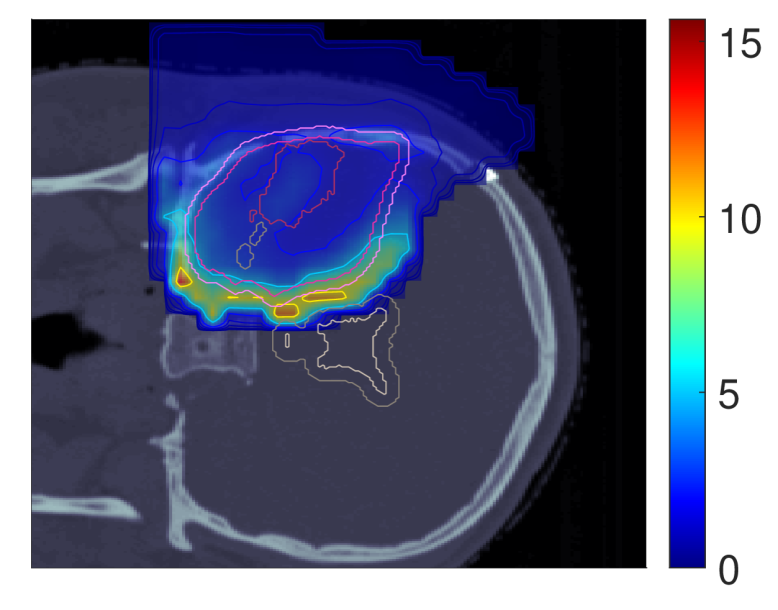

Figure 7 shows the POLO maps resulting from voxel-wise evaluation of the sigmoid-transformed linear predictor η\eta from Equation 1 with the input slice images for dRBE,fxd_{RBE,fx} and ldl_{d}.

NTCP30 %NTCP\approx{$30\text{\,}\mathrm{\char 37\relax}$} NTCP20 %NTCP\approx{$20\text{\,}\mathrm{\char 37\relax}$} NTCP10 %NTCP\approx{$10\text{\,}\mathrm{\char 37\relax}$}

Figure 7: Optimal slice images of the probability of lesion origin pp for NTCPpNTCP_{p}, LSEp~LSE_{\tilde{p}}, H~p\tilde{H}_{p} and H~p~\tilde{H}_{\tilde{p}} at different NTCP levels. Considering the slice images for dRBE,fxd_{RBE,fx} and ldl_{d} from Figure 3 and Figure 5, the calculated pp values can be deduced from the prediction model. For example, hot spots are primarily found where high dRBE,fxd_{RBE,fx} values meet high ldl_{d} values, and for the voxels inside the 4 mm4\text{\,}\mathrm{mm} ventricular fringe where bb boosts the probability prediction. We take from these results that the POLO model-based optimization of the LGG sample patient’s proton plan achieves its goal, i.e., reducing pp in the region of interest.

For NTCPpNTCP_{p} and H~p\tilde{H}_{p}, we observed a (slight) reduction of dRBE,fxd_{RBE,fx} in the target volume and in the lower region overlapping with the VS, as well as a redistribution of ldl_{d} from the target volume to the margin of the PTV. Correspondingly, we see an overall reduction of pp in the target volume, together with an increasing attenuation of the hot spots around the marginal region of the PTV, and an elimination at the lower end of the VS. At strong down-regulation of the NTCP, the values are approximately one order of magnitude smaller, with peaks in the intersections to the 4 mm4\text{\,}\mathrm{mm} ventricular fringe and in regions where dRBE,fxd_{RBE,fx} and ldl_{d} intensify.

LSEp~LSE_{\tilde{p}} showed a decay of dRBE,fxd_{RBE,fx} inside but not outside the target volume, and almost constant values of ldl_{d}, and we recognize this pattern again in the pp distributions: hot spots are softened by the isolation of high-dose and high-LET regions, and the pp values in the target volume follow the negative trend for dRBE,fxd_{RBE,fx} at lower NTCP levels. Even the “dose gap” that occurs at an NTCP of 20 %20\text{\,}\mathrm{\char 37\relax} in the upper part of the target volume can be read from pp. Last, for H~p~\tilde{H}_{\tilde{p}} we can correlate the results for dRBE,fxd_{RBE,fx} and ldl_{d} again to understand pp. The higher ldl_{d} along the PTV margin is reflected by larger pp values and local hot spots, while the region around the GTV exhibits smaller pp values due to the reduction of dRBE,fxd_{RBE,fx}. At the lowest NTCP level, dRBE,fxd_{RBE,fx} contracts around the GTV, leaving only a slightly upward region at the left margin of the PTV which resembles the high-LET region, and hot spots where dRBE,fxd_{RBE,fx}, ldl_{d} and bb interact reinforcingly.